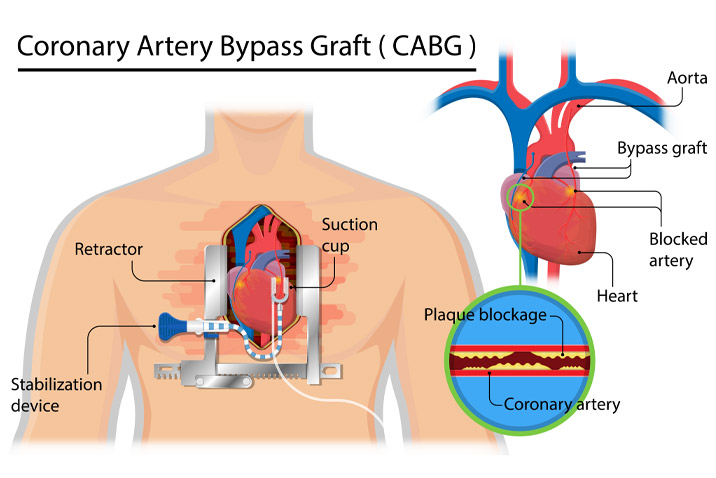

Overview

Package includes:

Days in hospital : 7 to 8 Days (For patient and one attendant)

Days in hotel : 12 Days (For patient and one attendant)

Room type in hospital : Shared

Room type in hotel : Private

Hotel category: Standard

Value added benefits of the CABG:

Ø Doctor consultation charges

Ø Lab tests and diagnostic charges

Ø Room charges inside hospital during the procedure

Ø Surgeon Fee

Ø Nursing charges

Ø Hospital surgery suite charges

Ø Anesthesia charges

Ø Routine medicines and routine consumables (bandages, dressings etc.)

Ø Food and Beverages inside hospital stay for patient and one attendant.

Extra benefits:

ü Interpreter

ü Visa assistance

Ø Site tourism of the city

Ø Follow up with the doctor

Ø Airport pick up and drop

Ø Free online consultation with the doctor

Ø Priority appointments with the doctor

Ø Room upgrade from sharing to private

Overview

Package includes:

Days in hospital : 7 to 8 Days (For patient and one attendant)

Days in hotel : 14 Days (For patient and one attendant)

Room type in hospital : Shared

Room type in hotel : Private

Hotel category: Standard

Value added benefits of the CABG and AVR:

Overview

Package includes:

Days in hospital : 7 to 8 Days (For patient and one attendant)

Days in hotel : 14 Days (For patient and one attendant)

Room type in hospital : Shared

Room type in hotel : Private

Hotel category: Standard

Value added benefits of the CABG and MVR:

Overview

Package includes:

Days in hospital : 7 to 8 Days (For patient and one attendant)

Days in hotel : 14 Days (For patient and one attendant)

Room type in hospital : Shared

Room type in hotel : Private

Hotel category: General

Value added benefits of the Double Valve Replacement and CABG:

Ø Doctor consultation charges

Ø Lab tests and diagnostic charges

Ø Room charges inside hospital during the procedure

Ø Surgeon Fee

Ø Cost of implant

Ø Nursing charges

Ø Hospital surgery suite charges

Ø Anesthesia charges

Ø Routine medicines and routine consumables (bandages, dressings etc.)

Ø Food and Beverages inside hospital stay for patient and one attendant.

Extra benefits:

ü Interpreter

ü Visa assistance

Ø Site tourism of the city

Ø Follow up with the doctor

Ø Airport pick up and drop

Ø Free online consultation with the doctor

Ø Priority appointments with the doctor

Ø Room upgrade from sharing to private